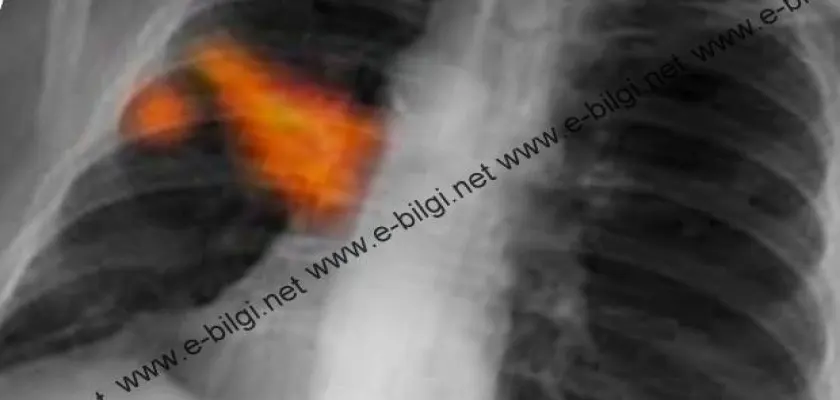

Akciğer Kanseri Nasıl Anlaşılır?

Akciğer kanseri tanısı çekilen basit bir akciğer filmi ile bile konulabilmektedir. Bu nedenle akciğer kanseri riski taşıyan (sigara içen, ailesinde akciğer kanseri olan ya da çalışma şartları nedeni ile risk taşıyan) kişilerin her yıl düzenli olarak akciğer röntgeni çektirmeleri gerekmektedir.